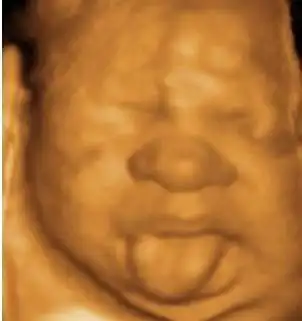

ai太牛了,上传一张四维照片,宝宝模样清晰可见,提前满足孕妈的好奇心

大咖科普四维三维二维超声有什么区别传说中的大筛查又是什么超声

二维三维四维预测宝宝长相.ai 现在真的特别奇迹,强大到让人 - 抖音